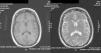

Caso clínicoMujer de 47 años, con diagnóstico de LES hace 10 años, con un brote de actividad renal un año previo a su ingreso, que ameritó tratamiento con micofenolato mofetilo (MMF) 3g al día, prednisona 1mg/kg con reducción hasta 0,5mg/kg/día, lográndose la remisión de la actividad. Ingresó con cefalea de inicio súbito, holocraneana, de intensidad 9 de 10 en la escala visual análoga; se agudizaba con el movimiento y sin mejoría con analgésicos, acompañada de fiebre y náuseas. En la exploración física, sin alteración del estado de consciencia, afectación de funciones mentales superiores o datos neurológicos focales y signos meníngeos negativos. Estudio de líquido cefalorraquídeo (LCR) con leucocitos 27/mm3 (80% mononucleares), eritrocitos 45/mm3, hiperproteinorraquia, normoglucorraquia, tinta china y tinción de Gram, negativas; IgM e IgG para citomegalovirus y herpes virus negativos. Sus estudios de laboratorio mostraron leucocitosis de 13 000 cél./mm3, con neutrofilia y monocitosis, niveles de C3 bajos con C4 normal, elevación de los títulos de anti-ADN, sedimento urinario con proteinuria, eritrocituria y cilindros negativos. Diagnóstico inicial de neuroinfección vs. actividad neuropsiquiátrica; se inició tratamiento empírico con ceftriaxona 2g cada 12h, vancomicina 1g cada 12h, aciclovir 600mg cada 8h, dexametasona 8mg cada 8h. En la resonancia magnética (RMN) cerebral se documentó, a nivel del lóbulo frontal, una lesión compatible con un absceso cerebral (fig. 1). A las 48h, el LCR se reportó incoloro, sin leucocitos, 15 eritrocitos, proteínas 39mg/dl y normoglucorraquia, PCR para M. tuberculosis, negativo. A los 4 días, se reportó crecimiento de LM en el LCR, hemocultivo negativo, cambiando el tratamiento a ampicilina 2g por vía intravenosa cada 4h por 6 semanas, con resolución completa del cuadro clínico sin secuelas. La RMN cerebral al mes mostró un área de impregnación nodular de 3mm de diámetro en situación frontal con mínimo edema adyacente. A los 4 meses, sin evidencia del proceso infeccioso (fig. 2).

RMN al momento del ingreso: los espacios de LCR, el cerebelo, bulbo, puente, mesencéfalo, cuerpo calloso y hemisferio derecho son normales. En el hemisferio izquierdo a nivel de la sustancia blanca profunda del lóbulo frontal se demuestra un área de hipo-hiperintensidad de señal en T1 y T2, respectivamente, de aspecto «edematoso», bilobulada que mide aproximadamente 17×6mm, circundada por edema vasogénico y que impregna intensa y anularmente tras la aplicación de contraste por vía intravenosa. Cambios compatibles con neuroinfección. Absceso bilobulado frontal izquierdo.